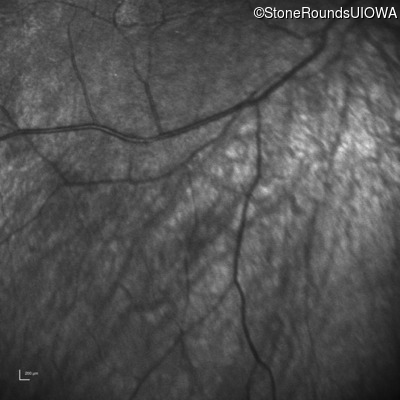

Infrared Fundus Photograph - Right -

No Light Perception

Exemplar

Expanded OCT Stack

×